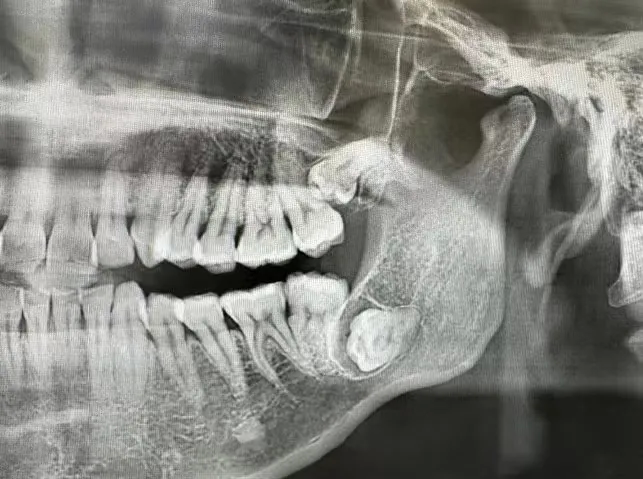

邻牙损坏:

智齿生长可能对邻牙造成挤压,导致邻牙损坏或移位。智齿与邻牙之间容易嵌塞食物,难以清洁,长期下来可能导致邻牙龋坏。

图片